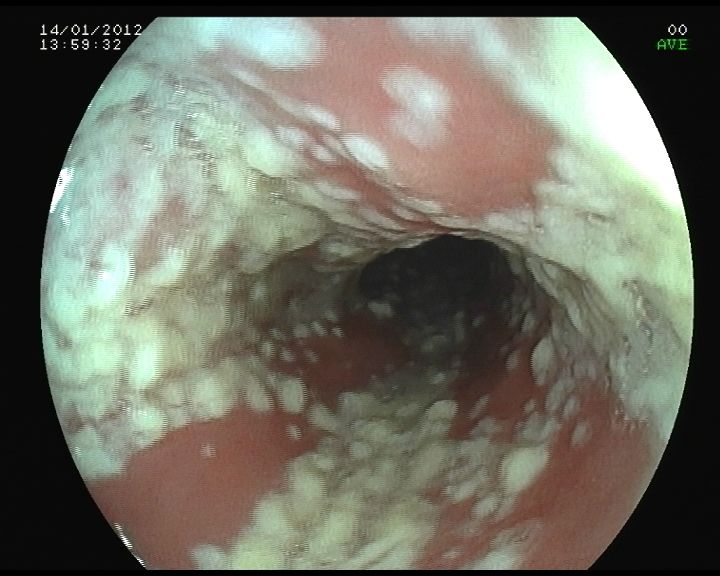

2. Esofágica

1. Fluconazol

1. Bucofaringea